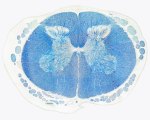

This image shows how blood is supplied to the spinal cord

Know your spinal cord – Anterior spinal artery syndrome » Spinal arteries

Published February 12, 2020 at 850 × 718 in Know your spinal cord – Anterior spinal artery syndrome